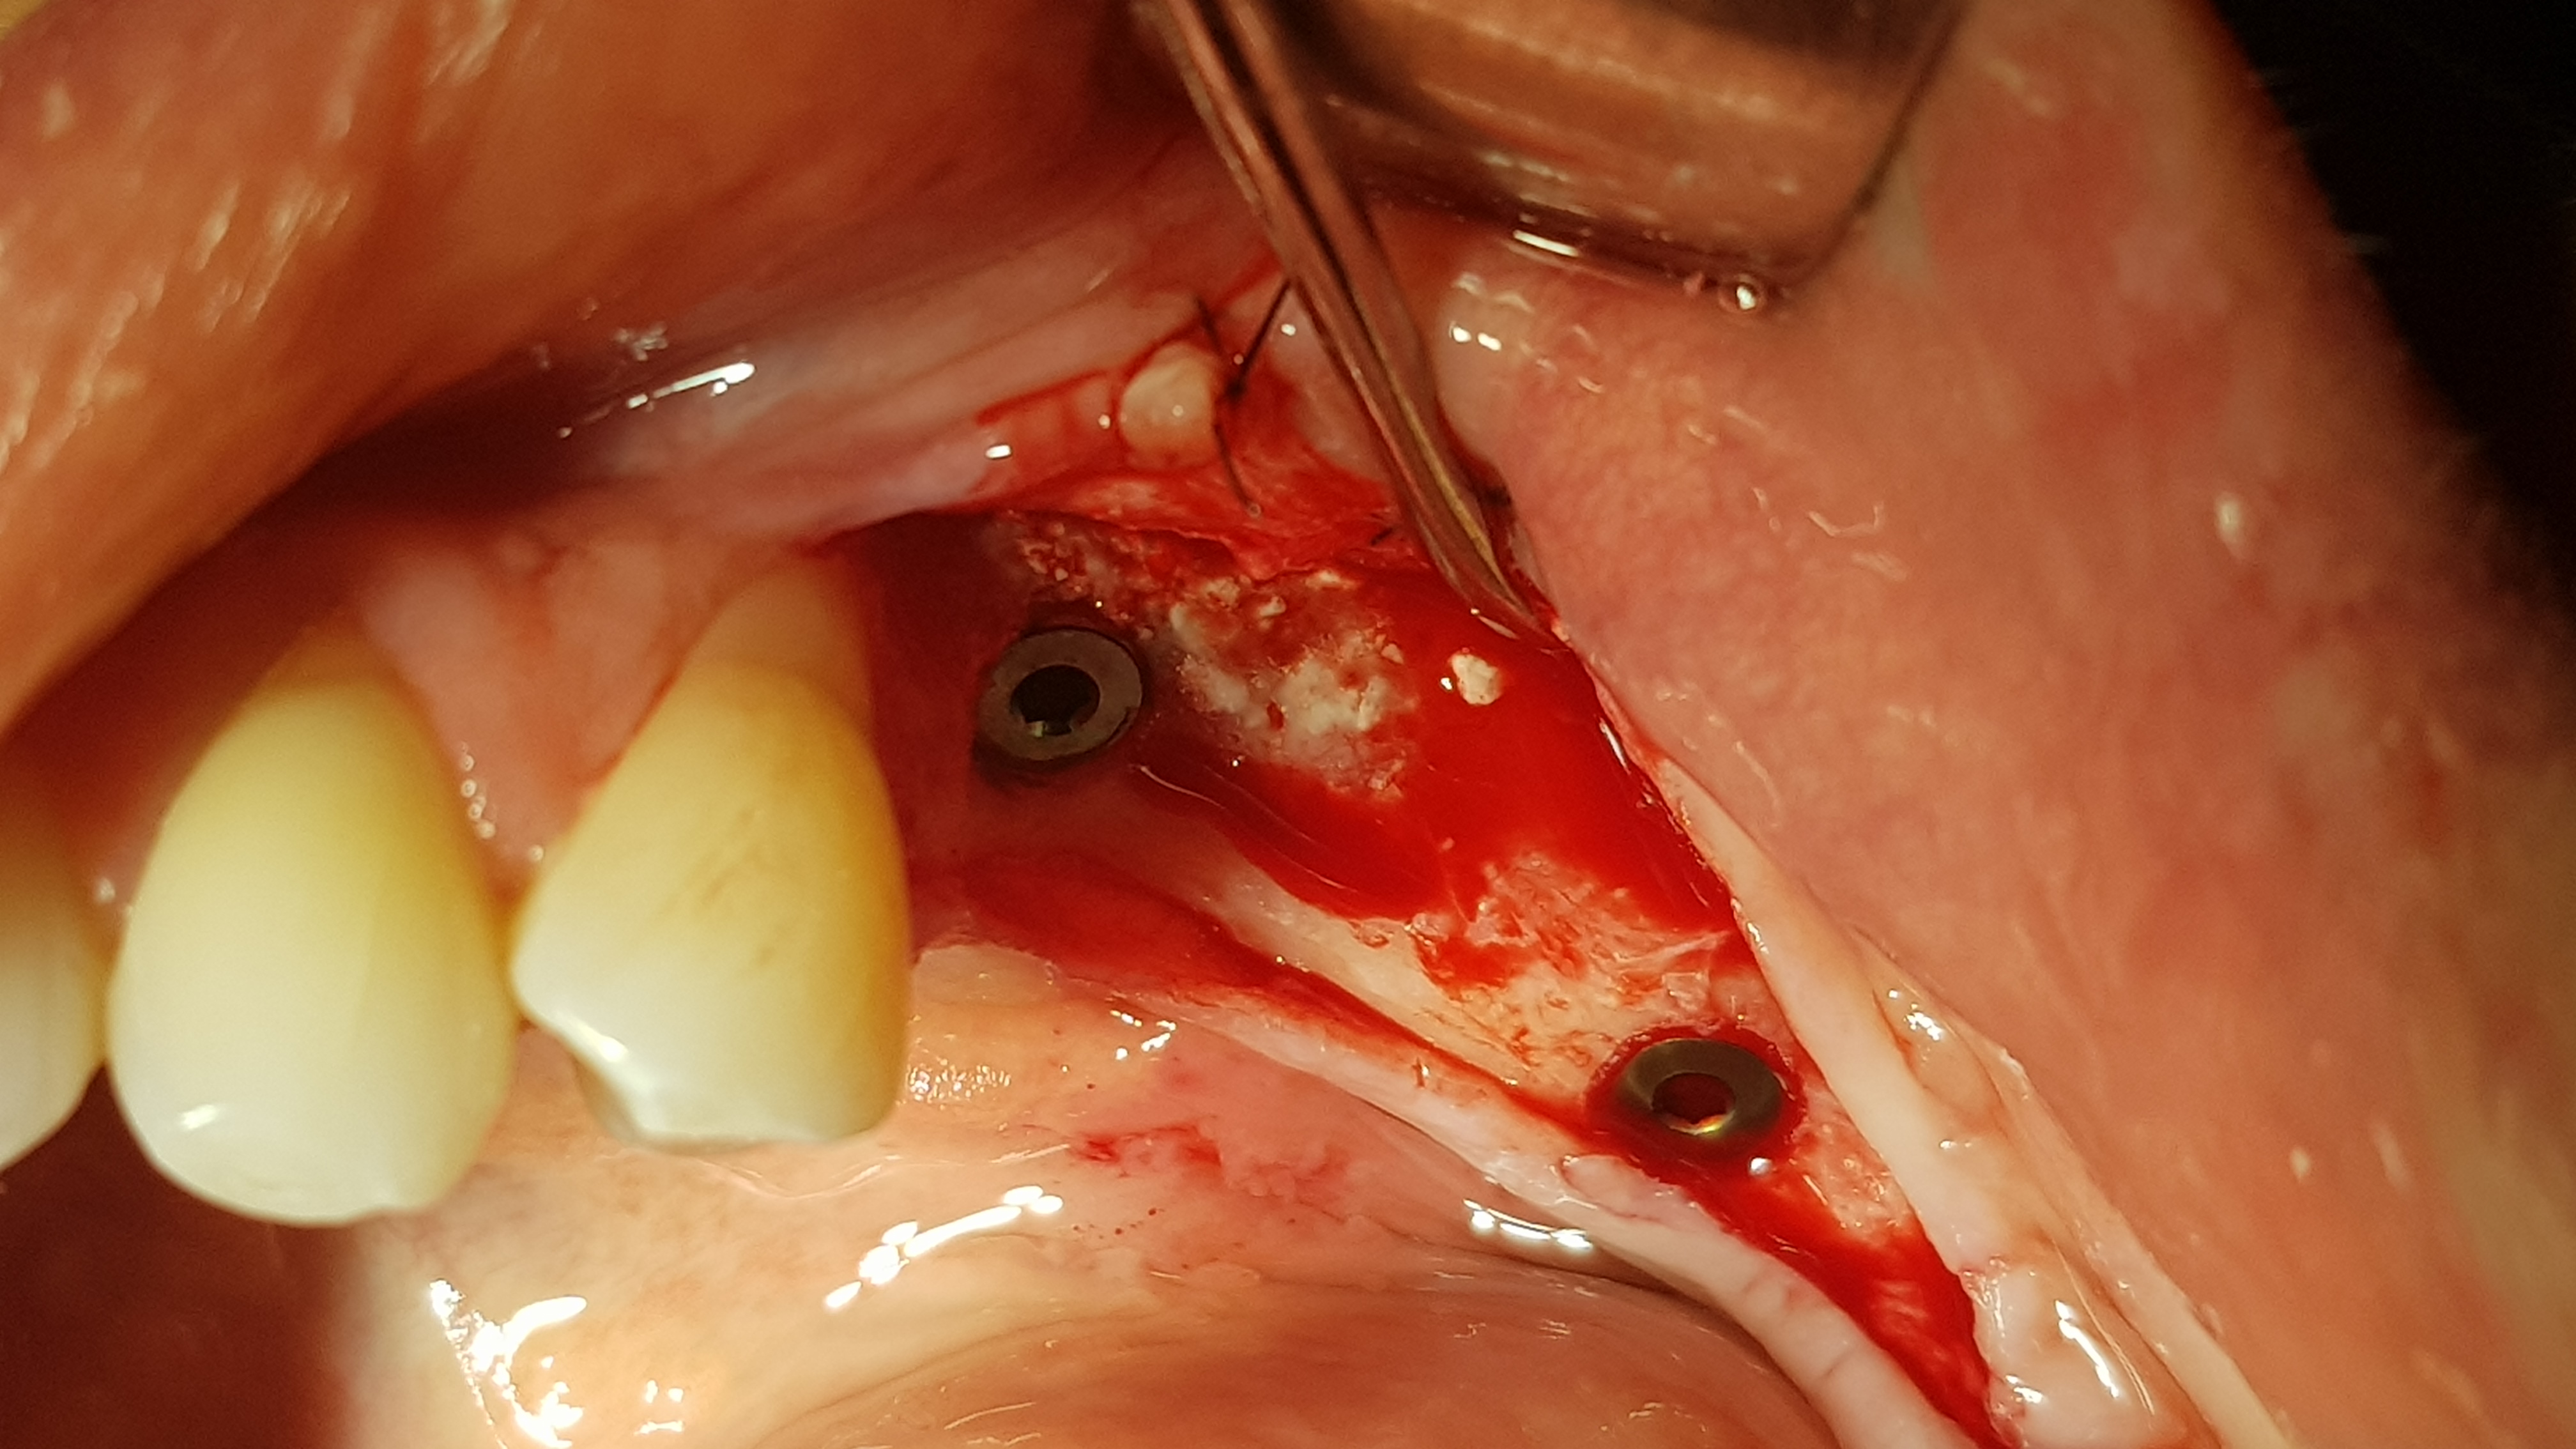

Regenerację blaszki przedsionkowej potwierdzono także klinicznie po odwarstwieniu płata podczas zabiegu planowej implantacji. Zmierzono szerokość wyrostka na poziomie 7-8 mm (ryc.14). Po wyrównaniu płaszczyzny wyrostka (ryc. 15) wykonano łoża dla implantów śrubowych w okolicy 45 (dł. 10 mm, śr. 3.7 mm) i 46/47 (dł. 10 mm, śr. 4.1 mm) (ryc.16), które wprowadzono w kość z momentem obrotowym około 25 Ncm. Ranę zaopatrzono szwami (PTFE – politetrafluoroetylen 4-0, igła odwrotnie tnąca, profil 3/8 koła długość 16 mm) (ryc.17).

Ryc. 14. Pomiar szerokości szczytu wyrostka w okolicy 45 wykazuje około 7 mm.

Ryc. 15. Pozycjonowanie implantów.

Ryc. 16. Wprowadzenie implantów w okolicy 45(3.7,10 mm) i 46-47( 4.1,10 mm). Ryc. 17. Zaopatrzenie rany.